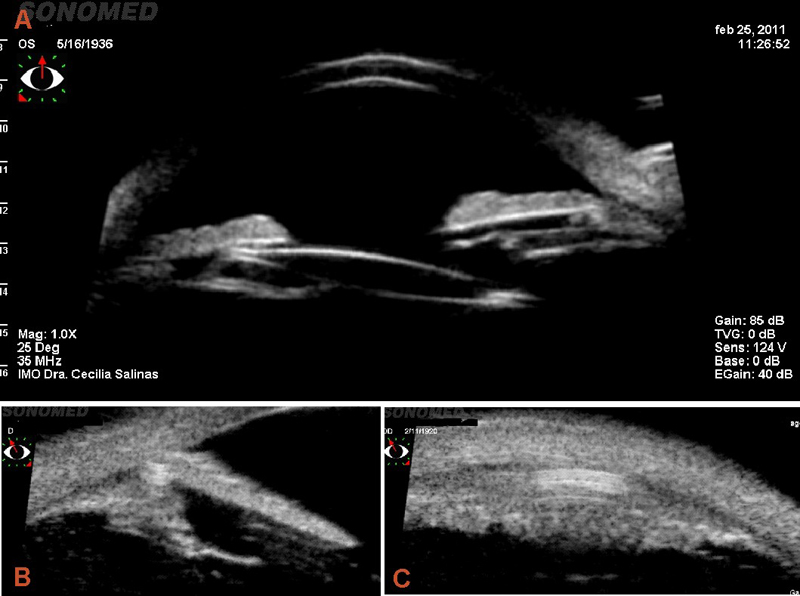

Melanoma de cuerpo ciliar: se hace evidente cuando es suficientemente grande y causa síntomas o se extiende a la coroides anterior o al iris. La BMU permite medir la altura y la base con cortes longitudinales y transversos (Figura 10 y Figura 11), pero existen otras características ultrasonográficas importantes9:

Figura 10. Melanoma de cuerpo ciliar. a) Corte longitudinal. b) Corte transverso. Es posible diferenciar el tumor del área hiperreflectiva de la esclera y pueden realizarse medidas para su seguimiento.

Figura 11. Gran melanoma de cuerpo ciliar que invade las estructuras vecinas penetrando por canales emisarios a la esclera (a) y desplazando el cristalino (b). Es posible medir la altura y la base transversa, y también valorar la reflectividad interna (c).